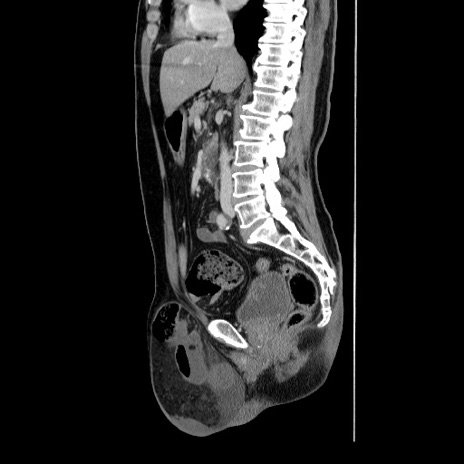

症例34(矢状断像)

【症例】60歳代 男性

【主訴】右鼠径部膨隆

【現病歴】1年程前より右鼠径部膨隆あり。自己にて還納可能だったため放置していた。3時間前より右鼠径部の脱出を認め、還納困難となり受診。

【身体所見】右鼠径部に小児頭大の膨隆あり。弾性硬であり、用手還納は困難。左鼠径部にも膨隆を認める。脱出はなし。